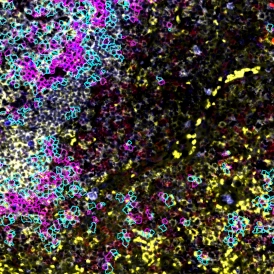

The IF Hi-Plex 50 App combines and analyses images of the same IF-stained tissue section, acquired up to 50 times with different markers. The App enables the detection of the cellular phenotypes of specific IF-stained cell populations. It segments cells into their nucleus, perinuclear area, and/or cytoplasm. Each segmented cell compartment is measured for up to 20 intensity, statistic, and morphometric parameters that can be displayed in and exported into scattergrams and histograms.